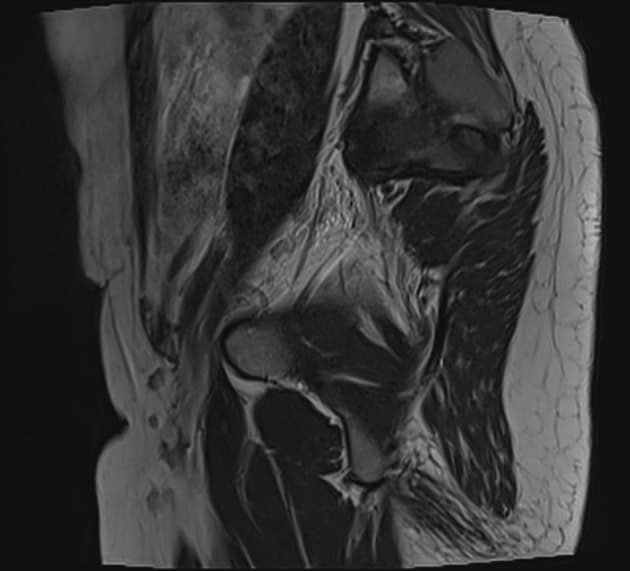

MRI cho thấy một tổn thương lạc nội mạc tử cung tại vị trí nối trực tràng - sigma (rectosigmoid junction) có biểu hiện dấu hiệu "mũ nấm" (mushroom cap sign).

Ngoài ra, còn phát hiện một tổn thương lạc nội mạc tử cung khác tại lớp thanh mạc phía sau tử cung, lan đến thành trước trực tràng.

Dày nhẹ vùng nối (junctional zone) của tử cung và các ổ thay đổi dạng nang nhỏ, phù hợp với hình ảnh tăng sản lạc nội mạc tử cung trong cơ tử cung (adenomyosis).

U lạc nội mạc tử cung (endometrioma) tại buồng trứng phải cũng được ghi nhận.

Vùng đáy có tín hiệu thấp của cấu trúc hình mũ nấm là tổn thương lạc nội mạc tử cung (dấu sao *), trong khi vùng mũ có tín hiệu cao đại diện cho niêm mạc và dưới niêm mạc (mũi tên), bị đẩy vào lòng đại tràng.

- Các đặc điểm hình ảnh cộng hưởng từ (MR imaging) của tình trạng lạc nội mạc tử cung rắn tại đoạn nối trực tràng - sigma bao gồm dấu hiệu "mũ nấm" (mushroom cap sign), được xem là một dấu hiệu đặc hiệu của tình trạng lạc nội mạc tử cung xâm lấn dạng rắn tại đại tràng sigma và trực tràng trên các hình ảnh cộng hưởng từ trọng T2 (T2-weighted MR images).

- "Dấu hiệu 'mũ nấm' trên cộng hưởng từ trọng T2 là dấu hiệu hình ảnh đặc hiệu của lạc nội mạc tử cung rắn tại đoạn nối trực tràng - sigma, biểu hiện tổn thương xâm lấn thành ruột và đẩy niêm mạc vào lòng đại tràng."